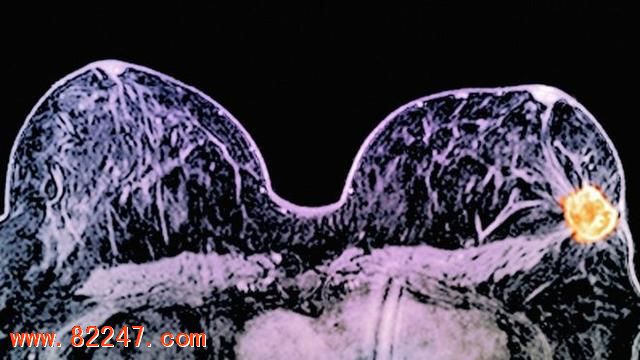

据 BBC 报道,英国医生发现有两种药物对于乳腺癌治疗有着明显的效果,这意味着某些女性将不再需要进行化疗。这些药物在 257 位女性患者的身上进行了测试,主要针对的是十分之一女性乳腺癌患者中的一种特定弱点。

研究中所使用的两种药物为拉帕替尼和曲妥单抗(也就是我们通常所说的赫赛汀),它们的治疗目标都是 HER2,这种蛋白会促使某些女性患者乳腺癌的增长。赫赛汀会作用在癌细胞表面,而拉帕替尼渗透到细胞内部来使 HER2 蛋白失去功效。

在不到两个周的治疗时间里,11% 的癌症患者体内的癌细胞完全消失,17% 的患者体内肿瘤缩小到不到 5 毫米。目前治疗 HER2 蛋白阳性乳腺癌的手段就是手术,然后进行化疗和赫赛汀治疗。